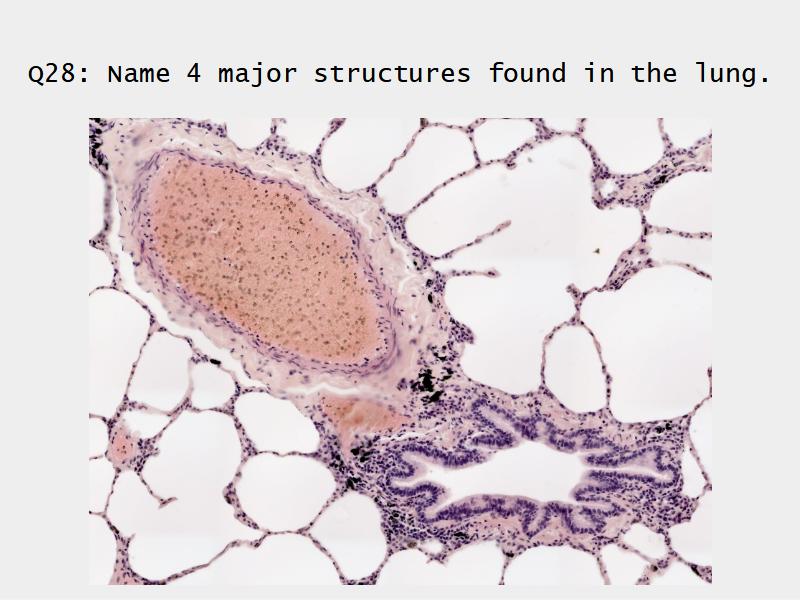

Slides: Respiratory System

- Slide 72 & 74: Lung

Bronchi - Transitions

- Intrapulmonary bronchi

- Irregular cartilage

- Respiratory epithelium

- Glands

- Bronchioles

- Smooth muscle REPLACE cartilage

- Ciliated columnar > Ciliated cuboidal

- NO glands - goblet cells -> secretory cells

- Terminal bronchioles

- Smooth muscle

- Ciliated cuboidal epithelium

- Secretory cells

- Respiratory bronchioles

- Conducting -> Respiratory

- Simple cuboidal epithelium

- Secretory cells

- Alveoli

Lungs